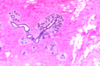

What is this?

Fibrocystic changes breast disease: apocrine metaplasia

What is this?

Fibrocystic change breast disease: ductal ectasia